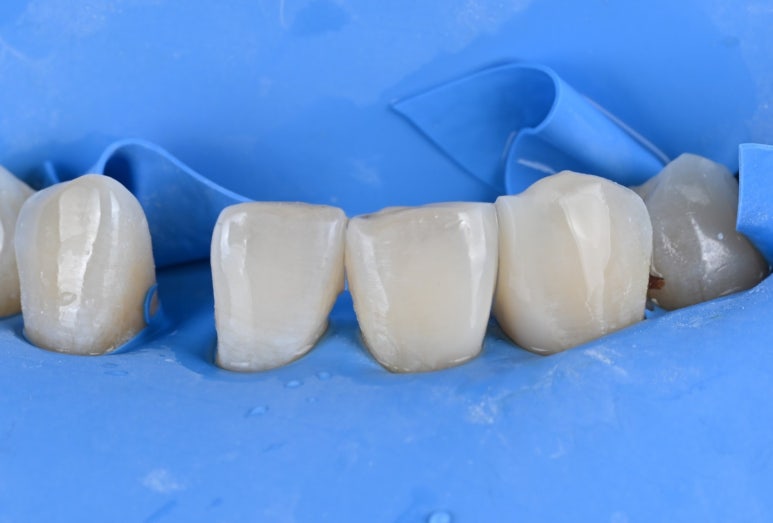

2) 넓은 공간은 메릴랜드 브릿지로

임플란트 대신 선택한 것은

'메릴랜드 브릿지'입니다.

일반 브릿지와 달리 치아를 전체적으로 깎지 않고,

인접 치아 안쪽에 얇은 날개 모양의

보철물을 붙여 치아를 연결하는 방식입니다.

덕분에 소중한 자연치아 삭제량을

획기적으로 줄일 수 있었습니다.

26.04.02 메릴랜드 브릿지 접착 준비

2) 정밀한 기공 제작

기공소장님과 긴밀히 소통하여

환자분의 치아 색상과 투명도를

자연치아와 유사하게 재현한

보철물을 의뢰했고, 정성스럽게 제작된

보철물을 확인했습니다.